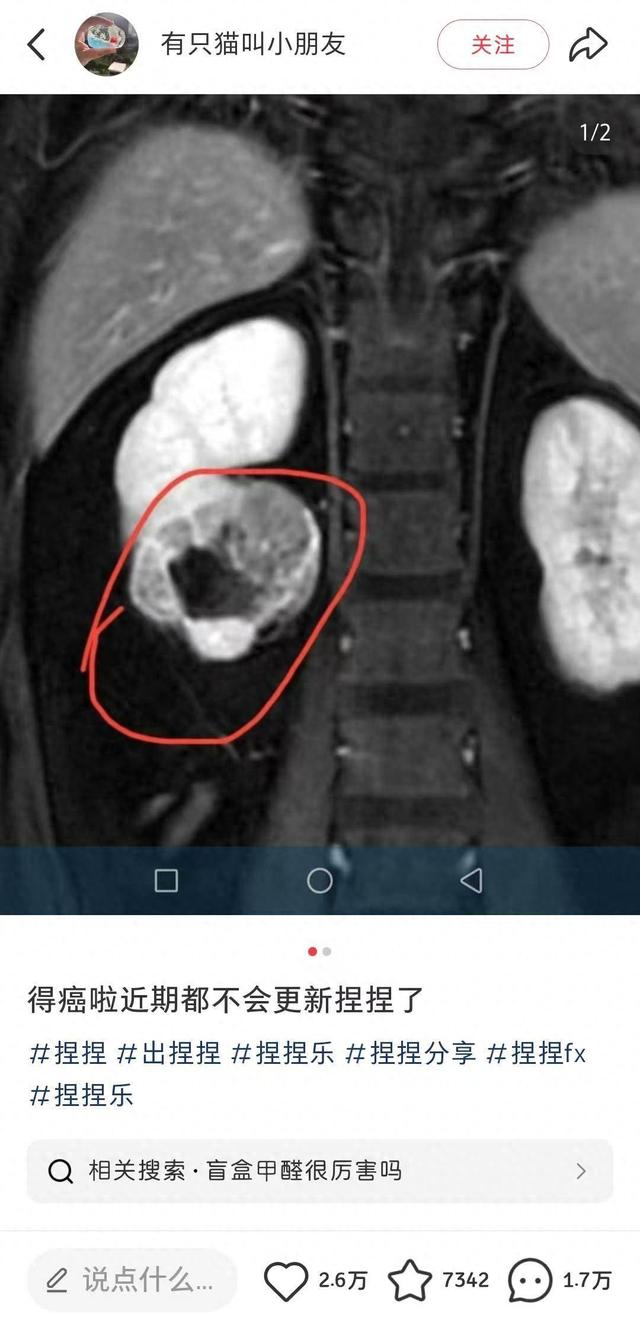

近日,一位ID名为“有只猫叫小朋友”的捏捏博主发文告诉粉丝:“得癌了,近期都不会更新捏捏了。”博主公开了自己的诊断病例,显示诊断意见为“右肾下级占位,肾ca可能,建议穿刺活检。”意味着医院给出的诊断是右肾下极区域出现异常组织占据,存在肾细胞癌的可能。